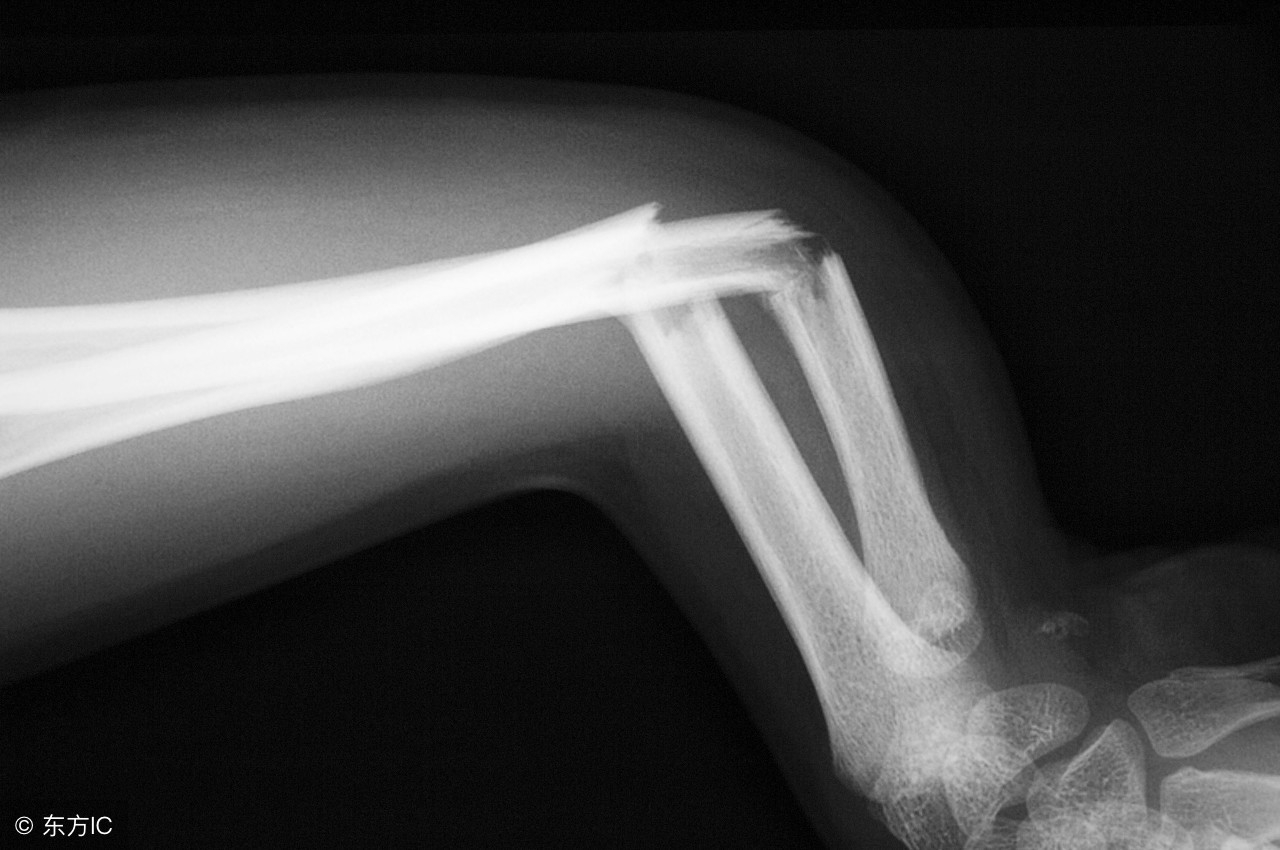

骨质疏松可表现为骨骼变脆、骨密度降低,在早期多无明显症状,后期可出现骨骼僵化、疼痛、身高缩短、驼背、脊柱畸形和伸展受限等现象,严重者可出现骨折。

骨质疏松是一种全身性的骨病,主要好发部位在脊柱、四肢长骨骨,骨质疏松性骨折则好发于桡骨远端、髋关节和腰椎等部位。